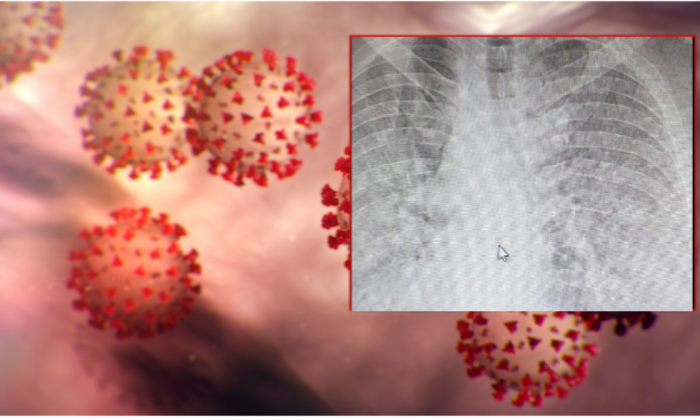

Drejtori i QKMF-së në komunën e Prishtinës, Sami Uka, sot ka njoftuar se një person i infektuar me koronavirus, i cili ka refuzuar hospitalizimin, po shkon në derë...